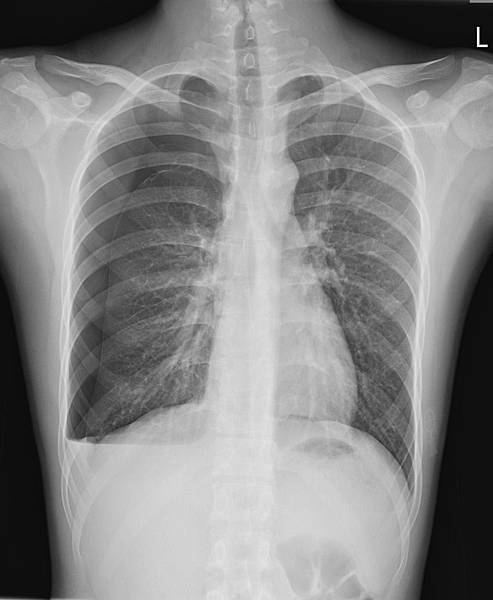

CXR才是診斷的經典:

右側橫膈下方有經典的Free air,

是胃/十二指腸或小腸或大腸破了!一個胃或腸的小破洞,電腦斷層無法判定哪兒破了,一般外科開下去發現是遠端降結腸(Distal descending colon)破了一個洞(0.5 cm),於是找直腸外科繼續完成手術。